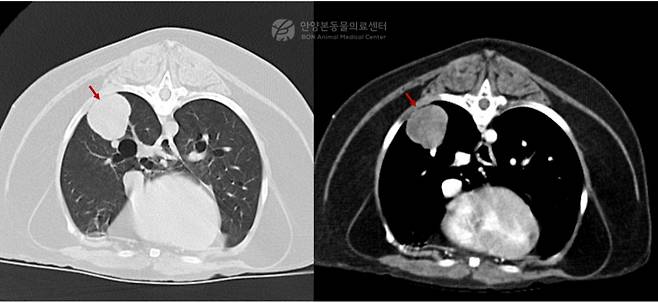

흉부 엑스레이 검사 결과 우측 폐 후엽 부위에서 약 2.5㎝ 크기의 연부조직 밀도 종괴가 확인됐다. 이후 보다 정확한 평가를 위해 CT(컴퓨터단층촬영) 검사를 시행한 결과, 동일 부위에 약 2.5㎝ 크기의 종괴가 확인됐다. 종괴는 인접한 폐혈관과 맞닿아 있고 일부는 흉막과 접촉하고 있었다.

다행히 흉강 및 복강 내 전이 소견은 발견되지 않아 외과적 절제가 가능한 상태로 판단됐다. 의료진은 종괴가 위치한 우측 폐 후엽을 제거하는 폐엽절제술을 계획했다.